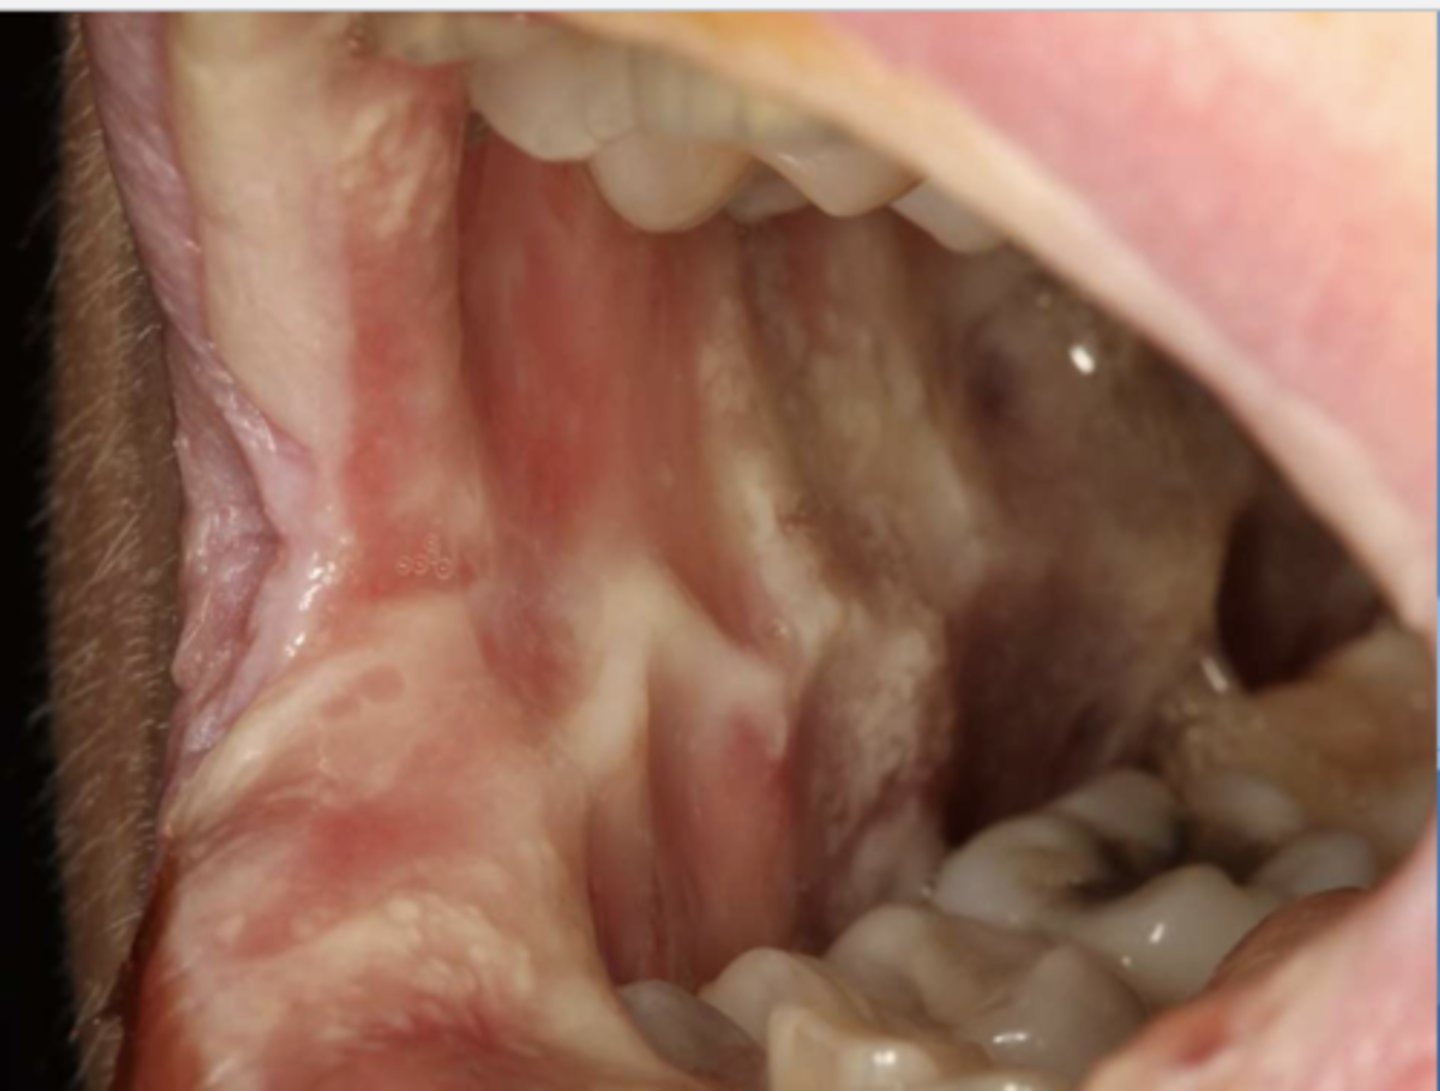

What do you suspect?

epulis fissuratum

What do the following clinical features describe?

-single or multiple folds of hyperplastic tissue in alveolar vestibule

-fibroepithelial poly/leaf-like denture fibroma may be seen along palatal mucosa